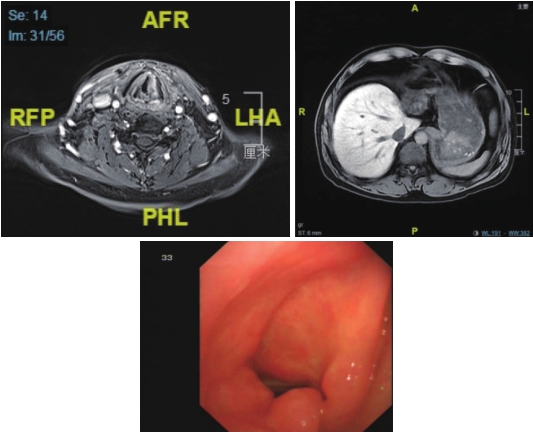

6疗程后:腹部MRI示,肝脏手术后改变,余腹部MRI未见异常。喉MRI示,左侧梨状窝占位及左颈肿大淋巴结基本消退。疗效评价为完全缓解CR。(图4、图5)

图4 喉MRI及腹部MRI(6疗程后)

梨状窝原发灶及颈部淋巴结已行根治性放疗,肝脏转移灶已切除

图5 喉MRI及腹部MRI(治疗结束后半年)

喉镜检查显示放疗后改变,提示完全缓解